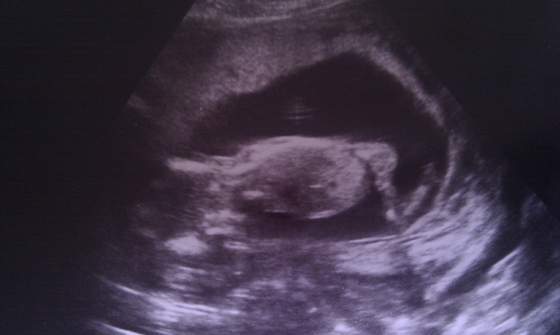

Wiec tak jak pisałam na ogólnym będziemy mieli chłopca

. Nasz synus całą wizytę kleczal na kolanach jakby pokutę odrabial

. Ogólnie wszystko w porządku. Idzie wszystko dokladnie tak jak wg terminu z OM. Maluch waży już 129 g i mierzy prawie 10 cm ( długość od czubkaglowy do pupy-bez nóżek). A oto fotki: